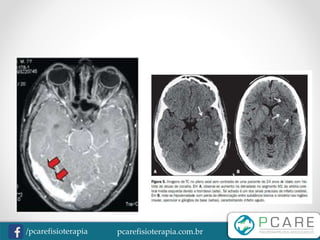

AVE Hemorrágico

• 10% dos casos

• Ruptura de um vaso intracraniano,

gerando o extravasamento de sangue

• Hemorragia Subaracnóidea

• Hemorragia Intraparenquimatosa

-TC de crânio